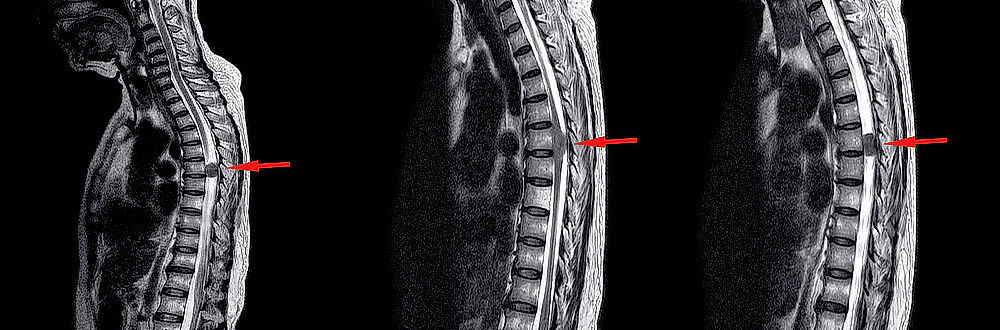

Odborníci rozlišují různé typy nádorů míchy, například podle místa jejich vzniku [1] (viz také obr. 1):

• extradurální nádory – nádory, které vznikly zevně od tvrdé pleny,

• intradurální extramedulární nádory – nádory, které vznikly uvnitř tvrdé pleny, nikoli však uvnitř samotné míchy,

• intradurální intramedulární nádory – nádory, které vznikly uvnitř samotné míchy (a proto i na vnitřní straně tvrdé pleny).

Obrázek 1: Klasifikace nádorů míchy podle místa jejich vzniku – schematický nákres. (Zdroj: By Mustapha Mansour, https://www.flickr.com/photos/134614741@N02/22133876283, CC BY-NC-SA 2.0)